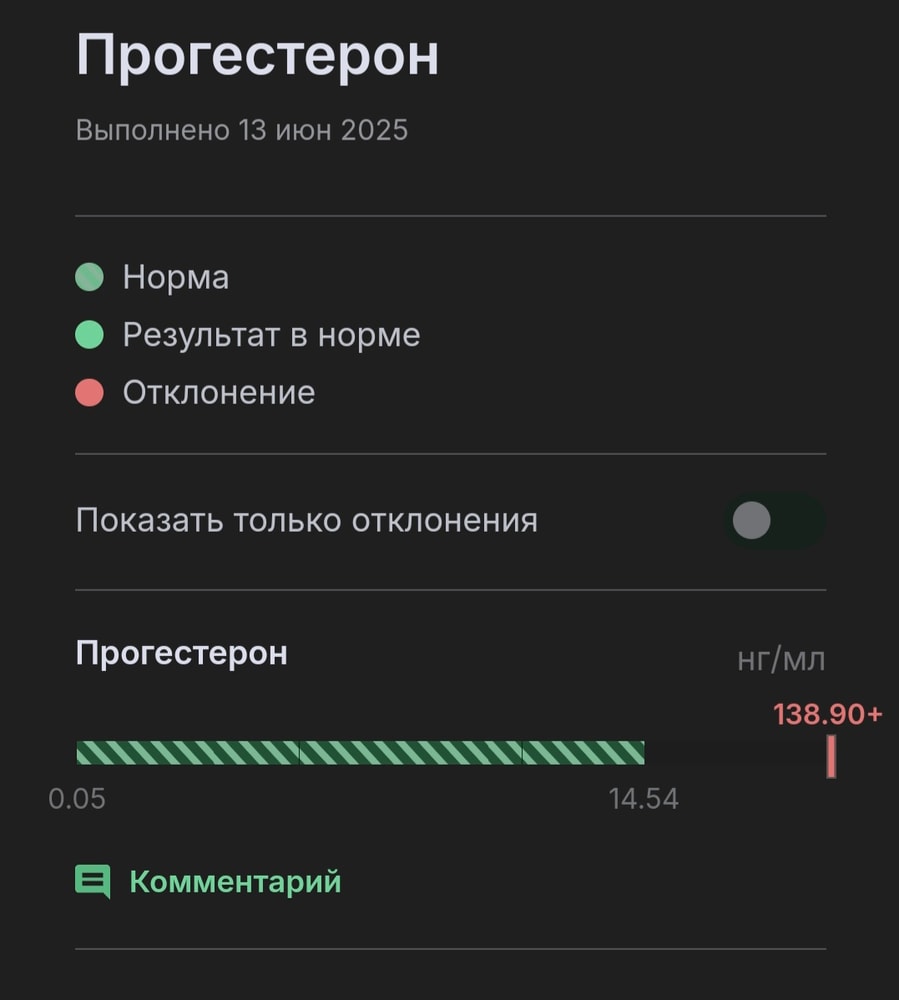

Хгч на 11 дпп трехневочки - 147,9